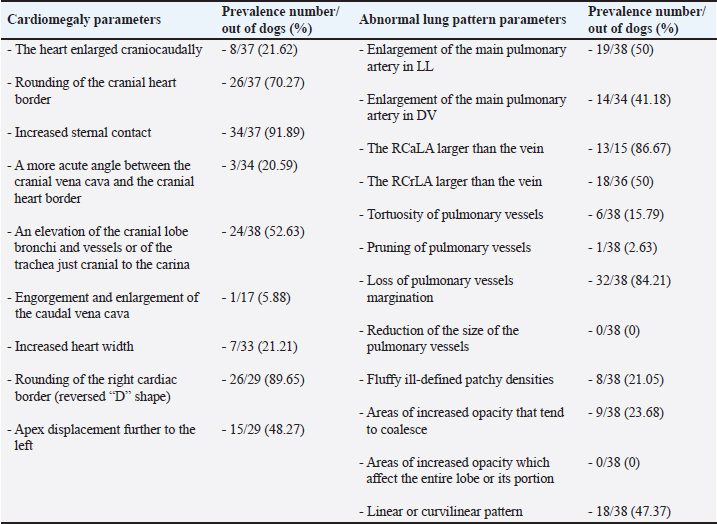

Typical vascular abnormalities include a bulging pulmonary artery segment and enlarged lobar pulmonary arteries, with peripheral pulmonary arteries becoming tortuous and truncated (Ackerman, 1987; Kittleson, 1998; Dunn, 2000; Polizopoulou et al., 2000). Arteritis lies at the root of enlarged arteries, to which PH may also contribute. Severe arteritis produces pulmonary artery tortuosity (Kittleson, 1998). Dead parasites act as pulmonary emboli, interrupting blood flow to lung segments, leading to the appearance of suddenly terminated pulmonary arteries, seen as blunted or pruned arteries (Kittleson, 1998). The enlargement of lobar pulmonary arteries, without concurrent venous distension, is strongly suggestive of HWD or other causes of PH (Ware, 2011). The right caudal lobar artery (RCaLA) is most commonly and heavily infested due to the effect of blood streaming toward this artery. Following the RCaLA, the left caudal lobar artery and subsequently, the cranial lobar arteries are the next commonly affected (Kittleson, 1998). Normally on radiographs, the VCC emerges through the diaphragm and slopes slightly cranioventrally towards cardiac caudal margin. It is similar in size to the aorta (Ao), but may get wider towards the heart (Herrtage and Denis, 1997). Enlargement of the VCC has been reported as a radiographic finding of right-sided cardiomegaly (Suter and Lord, 1984). Pulmonary parenchymal abnormalities vary from increased lung densities, seen in dogs with mild-moderate disease, up to generalized densities throughout the lung field (Kittleson, 1998). Parenchymal abnormalities, apparent especially after adulticide therapy, are seen as patchy alveolar densities (Dunn, 2000). Patchy pulmonary alveolar or interstitial infiltrates are the result of oedema, pneumonia, infarction, or fibrosis. Pulmonary opacities may be perivascular (Ware, 2011). Concerning heart remodeling, right ventricular enlargement is a characteristic radiographic feature (Dunn, 2000). This is a secondary change, arising as a consequence of PH. Right heart enlargement is seen in dogs with moderate to severe PH, and is best assessed on either the dorsoventral (DV) or ventrodorsal (VD) radiographic view (Lombard and Ackerman, 1984). Objective radiographic methods in HWD assess overall cardiac size and shape, and the size of blood vessels relevant to HWD in relation to various skeletal structures (intercostal spaces, vertebrae, sternebrae, thoracic inlet (TI), and etc.). The intercostal space method is based on counting the number of intercostal spaces that cover the heart silhouette (Buchanan, 1968; Buchanan and Bücheler, 1995). Although introduced a long time ago, it is still used, and like all other methods has its advantages and disadvantages. It is well known among clinicians and easy to use, because it is directly performed by counting the number of intercostal spaces while observing a dog’s lateral radiograph (LL). A normal heart silhouette has the size of 2.5 to 3.5 intercostal spaces, for deep-chested or wide-chested dogs respectively (Buchanan, 1968; Kealy, 1979; Owens, 1985). However, false negative and positive findings are possible due to thorax conformation, the position of the heart in the thorax, phase of respiration and position of the diaphragm, superimposition of ribs, and imprecise reference points (Buchanan and Bücheler, 1995). In 1995, the vertebral heart size (VHS) was introduced as an objective method, which expresses heart size through long axis (LA) and short axis (SA) normalized to the midthoracic vertebrae, starting from the fourth thoracic vertebra (T4) (Buchanan and Bücheler, 1995). In LL of dogs, the reference point for the cardiac LA is the ventral border of the left mainstem bronchus and the most distant ventral contour of the cardiac apex. This length reflects the combined size of the left atrium and left ventricle. The measured cardiac LA, made by using an adjustable caliper, is then repositioned over thoracic vertebrae beginning with the cranial edge of the T4. The distance to the caudal caliper point is then estimated to the nearest 0.1 vertebra (v). The maximal cardiac SA is measured in the central third region, perpendicular to the cardiac LA axis, and then also repositioned along thoracic vertebrae starting from the beginning of T4. The sum of LA and SA dimensions represent the overall size of the heart expressed as total units of vertebral length to the nearest 0.1 v. In DV or VD radiographs, the maximum LA and SA of the heart are determined with calipers in a similar fashion and measured against vertebrae in the LL radiograph beginning with T4 (Buchanan and Bücheler, 1995; Buchanan, 2000). The determined VHS in normal dogs is 9.7 ± 0.5 v in LL radiographs, and 10.2 ± 1.45 and 10.2 ± 0.83 v in DV and VD, respectively (Buchanan 2000). By using this method many studies have proposed breed-specific VHS reference values (Lamb et al., 2001; Gulanber et al., 2005; Bavegems et al., 2005; Marin et al., 2007; Castro et al., 2011; Jepsen-Grant et al., 2013). The following factors were found to influence mean VHS: interbreed variations, interobserver differences concerning references points of LA and SA, transformation into vertebral unit (v), and anomalies of thoracic vertebrae and intervertebral disc diseases (Hansson et al., 2005; Jepsen-Grant et al., 2013), cardiac cycle and, to a lesser extent, respiratory cycle (Olive et al., 2015). In order to overcome some of these limitations, modifications of this method, concerning the determination of reference points for SA of the heart and the introduction of the VHS unit (the length of one thoracic vertebra), have been proposed (Hansson et al., 2005; Spasojević Kosić et al., 2007; Costanza et al., 2022). The manubrium heart score (MHS) is proposed as the method that can overcome some limitations of the VHS method (Mostafa and Berry, 2017). In this method, the length of the manubrium (M) is used as a reference value to normalize the measurement of the height and width of the cardiac silhouette in right LL and VD thoracic radiographic views. On the LL view, the cardiac LA is measured from the ventral border of the carina to the caudoventral margin of the cardiac apex. The cardiac SA is measured on a line perpendicular to the LA at the widest point of the cardiac silhouette. On the VD view, the cardiac LA is measured from the distance of the right cranial margin of the heart silhouette to the cardiac apex, and the SA heart axis is measured at the widest line perpendicular to the LA. The M length is measured as the maximum M length on the right LL view. The reason why the M of the sternum is selected is that it is relatively prominent, easily identified, and measured on LL radiographs. At the same time, an evenly elongated, bullet-shaped, rectangular, or camel head-neck-shaped M is accepted for the MHS measurement. However, if the M of dogs is abnormal or its cranial edge cannot be identified, the calculation of the MHS is not possible. Established values of the MHS in normal healthy dogs vary from 4.8 ± 0.5 to 5.3 ± 0.8 in LL view, and from 5.4 ± 0.6 to 5.8 ± 0.9 in VD view in large and small dogs, respectively (Mostafa and Berry, 2017). Furthermore, the MHS is recommended as a useful, objective method for heart disease screening in dogs, capable of distinguishing between left-sided and right-sided cardiomegaly (Mostafa et al., 2020). In addition to MHS, the cardiac sphericity index (CSI) is another measure of the shape of the heart, which can be used to assess the globe-shaped heart. It is calculated by dividing the cardiac SA by the cardiac LA. The value of CSI≥1.00 means a near round figure of the cardiac silhouette (Guglielmini et al., 2012). Recently, the sternebral heart scale was proposed for the assessment of heart size in ferrets (Gutiérrez et al., 2022). Upon determination of cardiac LA and SA in radiograph views, the LA and SA of the heart are measured along the sternum, starting at the cranial edge of the fourth sternebra (S4). The sum of the cardiac LA and SA is expressed in sternebral units (s), estimated to an accuracy of 0.1 seconds. Thus, it determines the sternebral heart size (SHS) in this species. This method overcomes the limitation of the MHS caused by the abnormal shape of the M or the impossibility of cranial margin M line identification (Gutiérrez et al., 2022). Although the correlation between heart size and sternebral length was slightly lower compared to the correlation with the vertebral length in dogs (Buchanan and Bücheler, 1995), to the best of our knowledge, no study on the subject of the normal SHS in dogs has been published yet. First proposed as a reference point to assess tracheal diameter in brachycephalic and non-brachycephalic dogs (Harvey and Fink, 1982; Mostafa and Berry, 2022), the TI has recently been assessed as a unit for measuring thoracic inlet heart size (TIHS) (Marbella Fernández et al., 2023a). In this study, the TIHS has proved to be a simple and accurate method for measuring heart size, which overcomes some limitations seen in previously mentioned methods, such as vertebral or M malformations, and variations due to dog’s size and breed. Reference points for the cardiac LA and SA in this method are like the ones described for the VHS. Upon being measured the cardiac LA and SA are summed and divided by the corresponding TI length. The TI, defined as the minimum length of the TI, is determined as the distance between the cranio-ventral aspect of the first thoracic vertebra and the cranio-dorsal margin of the M at its highest point. The mean TIHS value for normal dogs is 2.86, and a TIHS value above 3.2 is considered to be an increased heart size in dogs (Marbella Fernández et al., 2023a). Besides methods based on linear determination of cardiac size through its LA and SA, which are then expressed by different skeletal structures, methods based on the estimation of cardiac areas have also been investigated. One of these modalities for cardiac size evaluation is the ratio between cardiac and thoracic areas (Torad and Hassan, 2014). Determination of the cardiothoracic ratio derived from LL thoracic radiographs (Empel and W, 1974) or on both LL and VD radiographs after peak inspiration and expiration (Castro et al., 2011; Torad and Hassan, 2014). Another way of assessing heart size is to compare the heart area to the T4 body area (So et al., 2024). These methods showed not only a correlation with VHS (Azevedo et al., 2016; So et al., 2024), but also, and to a higher extent, with the cardiac volume measured by computed tomography (So et al., 2024). However, these methods are complicated and require specific software, not always available in clinical practice. In addition, thoracic cavity conformation varies in different dog breeds, and individual changes in healthy and diseased animals (Buchanan and Bücheler, 1995; Castro et al., 2011; Torad and Hassan, 2014) make these methods of limited use. Blood vessels relevant to HWD (RCrLA, RCaLA, VCC) can also be assessed objectively, by comparing them with different skeletal structure, or, in case of the VCC, with the Ao. The width of the RCrLA on a LL view in normal dogs should not exceed the narrowest diameter of the 4th rib (4.r). On DV radiographs, the width of the RCaLA is normally not larger than the 9th rib (9.r) at the level of their intersection (Herrtage and Denis, 1997; Ware, 2011). Furthermore, ratios of RCrLA/4.r≥ 1.08, and RCaLA/9.r≥ 1.10 indicate the presence of PH, and thus show potential as a preliminary screening tool for PH in HW-infected dogs (Falcon Cordon 2024a). The measurement of VCC size and its ratio towards other fixed-sized surrounding structures, such as the length of vertebrae at the level of tracheal bifurcation, the descending Ao, and the width of the 4.r can help in the detection of right-side heart disease in dogs (Arya et al., 2021). The diameter of VCC should be considered normal in a dog with a ratio of VCC/Ao < 1.00, VCC/ v < 0.80, or VCC/4.r < 2.25 (Lehmkuhl et al., 1997). Material and MethodsData used in this study related to client-owned dogs in which HW infection was identified. For this purpose, the medical records of these dogs were reviewed with the collection of all data relevant for the retrospective radiographic analyses. The material for this study included radiographs of 40 dogs naturally infected with D. immitis. There were two criteria for this study. The first one was a complete HW infection diagnosis performed in these dogs (detection of antigen of adult parasite D. immitis and modified Knott test). The second criterion was that the dog had either LL or both (LL and DV) radiographs recorded without the use of sedation or anesthesia. While in 4 dogs only LL radiographs were available, in all others, both LL and DV radiographs were used for analyses. The dogs were of different age, gender, and breed. The average age of the dogs was 6.36 ± 3.68 years, and there were 12 females and 28 males belonging to different breeds (German Shepherd, Belgian Shepherd, Labrador Retriever, Golden Retriever, Rottweiler, Boxer, Dobermann, American Staffordshire Terrier, American Pit Bull Terrier, Great Dane, Dogo Argentino, Cane Corso, Hungarian Vizsla, German Hunting Terrier, Breton Spaniel, and mixed-breed dogs of small and medium size). For 8 out of these 40 dogs, radiographs of both projections (LL and DV) were available at the moment of the HWD diagnosis (before therapy) and at the end of successful therapy (after therapy). The alternative therapy (doxycycline and ivermectin) (Spasojević Kosić et al., 2024) was used as the HW infection therapy in all eight dogs. The dog was considered cured of HWD if clinical signs have disappeared and if no D.immitis antigenemia and microfilariaemia have been detected. At that time the post-treatment radiographs had been recorded. Thoracic radiographs were obtained using Eickemeyer Hiray Plus, Porta 100HF, with the exposure settings 46/2,5 kVp/mAs - 80/2,5 kVp/mAs, with a focal film distance of 75 cm (Primax flm RTG - G, 30x40, and DR system - Exam VueDuo). Each radiograph was submitted to subjective and objective assessment. Any difficulties which disabled predefined methodology of subjective parameters identifications and of objective measurements were considered as feasibility limitation criteria. All radiographic assessments were done by an experienced veterinary cardiologist. The radiographic assessments were done after being triple check before the final decision. Parameters relevant for subjective radiographic assessment were classified as radiographic features for right-sided cardiomegaly and abnormal lung patterns (Table 2). Table 2. Specific parameters of cardiomegaly and abnormal lung patterns in the subjective radiographic assessment for the HWD.

Fig. 3. Radiographs of two dogs with the most severe changes. 3A and B - LL and DV views of a 9-year-old female Rottweiler. Massive opacities can be seen in the ventral areas of the cranial, middle and accessory lobes (in LL view), and in the left cranial, right cranial and caudal and accessory lobes (in DV view). These changes cover the heart silhouette. Also, reduced flows to the left caudal and right middle lobes can be seen. In the caudal lobes in LL view, and in the right caudal lobes in DV view, air alveolograms can be seen. 3C and D - LL and DV views of a 5-year-old female mix-breed dog: Massive opacification in the ventral areas of lung lobes in LL view made it impossible to define the heart silhouette. The trachea lies almost parallel to the spine, with a mixed interstitial-alveolar pattern of the caudal lung lobes. On the DV view diffuse opacities in lung lobes prevent cardiac silhouette and vascular pattern assessment. The radiographs of all other dogs were considered suitable for assessment both subjectively and objectively. Aside from 4 dogs, in which only LL were available, there were also two dogs in which opacity in their lung field in their DV radiographs enabled only the assessment of some subjective and objective parameters. The most prevalent features of subjective radiographic assessment (Table 3) of the HWD in these dogs were the increased sternal contact (91.89%), the rounding of the right cardiac border (89.65%), and the RCaLA larger than the vein (86.67%). Radiographs of almost all the dogs (37/38 dogs or 97.37%) or all of them (38/38 dogs or 100%) were eligible for assessment and detection of the more prevalent parameters of cardiomegaly (increased sternal contact, rounding of the cranial heart border) and abnormal lung field (loss of margination of pulmonary vessels). However, not each of the subjective assessment parameters could be analyzed in all the dogs. In 55.88% of the dogs (19/34 dogs), it was not possible to compare the width of the RCaLA and the corresponding vein. The most common reasons were one or several of these: unclear vein margins, opacity of the surrounding lung field, incorrect dog position. In 55.26% of the dogs (21/38 dogs), it was not possible to define whether the VCC is larger than the Ao due to the dogs’ respiratory cycle (position of the diaphragm) at the time of radiographic recordings, the opacity of surrounding tissues and not clearly visible margins of the Ao. In one dog (5.88% of dogs), VCC was wider than the Ao. Table 3. Prevalence and feasibility of subjective radiographic features in the dogs with HWD.

When we statistically analyzed the subjective radiographic parameters in the dogs with HWD before and after therapy, no statistically significant difference was registered in the occurrence of cardiomegaly parameters. However, among the subjective parameters of abnormal lung patterns, the enlargement of the main pulmonary artery in LL (p=0.0256), the loss of margination of pulmonary vessels (p= 0.0203), the areas of increased opacity that tend to coalesce (p= 0.0385), have shown significant differences before and after therapy in the dogs with HWD. The FDR post hoc analysis showed that the enlargement of the main pulmonary artery in LL (p ≤ 0.033, FDR), and the areas of increased opacity that tend to coalesce (p ≤ 0.05, FDR) had the significant lower occurrence after therapy. Objective measurements of cardiac size and shape were done in different number of dogs depending on the methods used (Table 4). VHS could not be determined in 2 and 4 dogs in LL and DV, respectively. The reason for this was lung opacity, which prevented heart silhouette determination. The same reason for the feasibility of SHS and CSI in LL and DV views was noted in an equal number of dogs. However, the number of dogs in which it was not possible to determine MHS and TIHS was higher, mainly due to incorrect positioning of the dogs and the impossibility of cranial M margin determination. Table 4. Cardiac size and shape in the dogs with HWD measured by different objective methods.